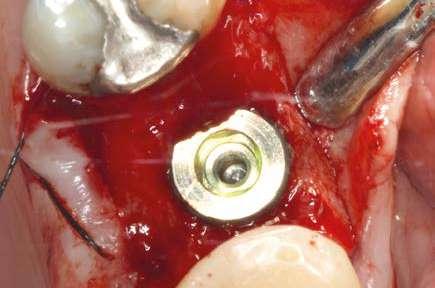

PROTOCOLOS DE AUTOTRASPLANTE POSEXTRACCIÓN: ¿INMEDIATOS

O DIFERIDOS?

El autotrasplante dental se está convirtiendo en una opción predecible en la odontología restauradora contemporánea. Sin embargo, las condiciones del alvéolo receptor pueden variar notablemente según el momento de la pérdida del diente y el tipo de diente a extraer. El objetivo de este artículo es presentar protocolos de autotrasplante posextracción basados en la planificación digital y describir los criterios de selección para cada una de las diversas opciones.

Introducción

El autotrasplante consiste en la extracción de un diente de su posición original y su posterior colocación en una posición distinta de la arcada dentaria del mismo paciente (Natiella y cols. 1970). Para realizar este procedimiento quirúrgico se pueden utilizar dientes donantes que estén erupcionados, dientes impactados o parcialmente impactados, independientemente del grado de formación radicular (Plotino y cols. 2020). Además, el autotrasplante puede realizarse tanto en situaciones posextracción inmediata como en alvéolos que hayan sido previamente preparados de forma quirúrgica (Abella y cols. 2021a).